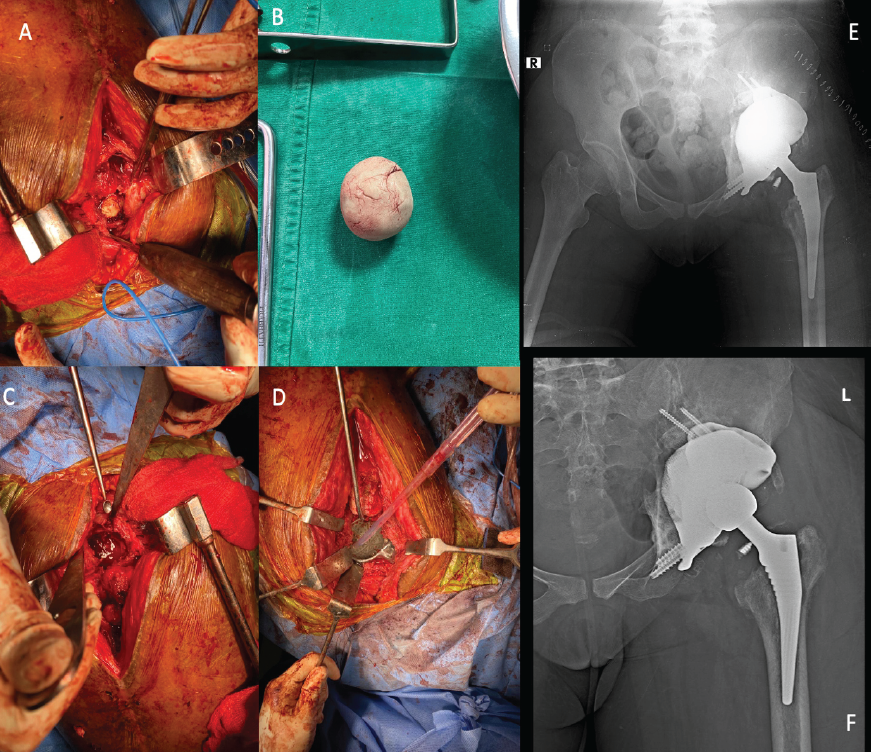

Twelve weeks after stage one, revision reconstruction was performed through the same approach. The cement spacer was removed and bony spurs were excised. The patient-specific 3D-printed acetabular component with augments was implanted and secured using pelvic and acetabular screws under fluoroscopic guidance. An acetabular liner, modular femoral head and neck, and an uncemented femoral stem (Latitud, Meril Life, India) were inserted. Intraoperative assessment demonstrated stable fixation and a satisfactory range of motion. Layered closure was completed in the standard fashion.

Postoperatively, the patient demonstrated a residual limb shortening of approximately 1 cm, which was successfully managed with a heel raise (Fig. 6). There were no early complications. Weight-bearing was intentionally delayed and ambulation initially commenced with non-weight-bearing walking alongside mobility-focused exercises. This was followed by a structured strengthening program over 10 weeks, progression to partial weight-bearing for the subsequent 6 weeks, and eventual transition to full weight-bearing. During this period, the patient’s visual analog scale pain score improved from 8 to 3 and the Harris Hip Score increased from 30.45% to 60.65%. Unfortunately, the patient was lost to follow-up after 6 months.

Figure 6: (a and b) The removal of cement spacer. (c) The defect in the acetabulum. (d) The placement of the customized three-dimensional (3D)-printed implant in situ. (e) The immediate post-operative radiograph after fixation of the customized 3D-printed implant with revision total hip replacement. (f) The follow-up radiograph after 6 months.